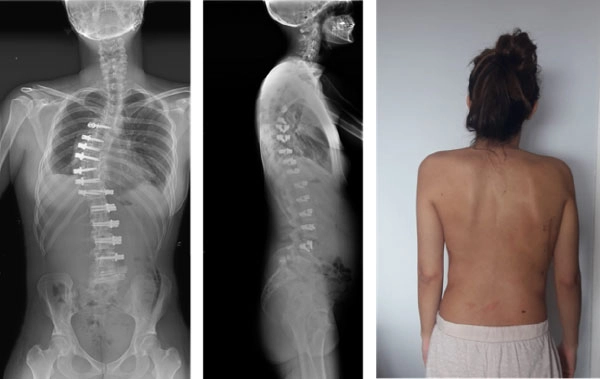

9月19日は手術見学が中止となってしまいサグラダファミリアなど市内観光を行い、9月20日はClinica Sagrada FamiliaにてJuan Carlos Rodriguez Olaverri先生の側弯症に対するAnterior scoliosis correctionというnon-fusion surgeryを見学させてもらいました。Lenke Type 3の20台女性の側弯症の症例に対し、開胸でのMain thoracic curveの矯正の後、後腹腔アプローチにてthoracolumbar curveの矯正を行いました。椎体スクリューを前方に挿入し、ポリエチレンテープで側弯矯正を行うという、不勉強の為初めて見知る術式でしたが、Olaverri先生自身も14例目の執刀ということで夕方まで手術をされていました。20台の症例でカーブ自体も硬く、challengingな症例だとおっしゃっていました。Apex周囲の椎間板は側弯矯正のため切除しており、長期的な経過を知りたいところです。その後助手をされていたneurosurgeonの先生がTarlov Cystの手術を予定されており、非常に興味深かったですが残念ながら時間切れで手術見学はできませんでした。

AIS Age26 術前

AIS Age26 術後